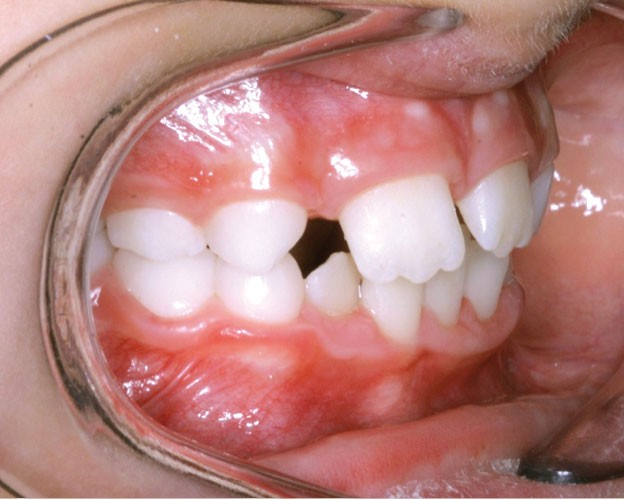

Les vues endo-buccales après extraction de 52 montrent des relations occlusales de classe II, un léger encombrement incisif mandibulaire et une tendance à la fermeture spontanée des espaces des incisives latérales confirmant le choix thérapeutique d’une fermeture d’espace (fig. 2).